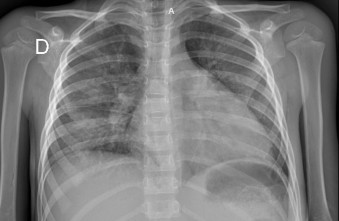

En los exámenes de laboratorio al momento de la hospitalización se evidenció falla hepática con hipertransaminemia moderada (TGO = 661U/L, TGP = 187U/L, BT = 5,20 mg/dL, BD = 2,056 mg/dL, Alb = 1,75 g/dL), perfil de coagulación severamente alterado (TT = 33,8", TP = 22" 48 %, TTPA = 52,7", fibrinógeno = 78 mg/dL, INR = 1,68, dímero D 10,34 ug/dL). El hemograma mostró leucocitos = 13 000, neutrófilos = 6210, linfocitos = 5,8, hemoglobina = 8,4 g/dL, hematocrito = 25,7 % y plaquetas = 422 000. PCR = 20 U/L, DHL = 2100 U/L, ferritina = 2000 mg/L. Los resultados de la ecografía abdominal revelaron hepatoesplenomegalia; los de radiografía de tórax, derrame pleural en las bases de ambos hemitórax.

Asimismo, presentaba DHL = 1087, ferritina = 2000, PCR = 1,53. Recibió catorce días de antibiótico, nueve días de albúmina, furosemida de dosis continua por tres días y luego en bolos después de la administración de albúmina. Al día siguiente, presentó dificultad respiratoria, por lo que se tomó una radiografía de tórax, donde se evidenció cardiomegalia y congestión pulmonar. El médico cardiólogo diagnosticó insuficiencia cardiaca congestiva por miocardiopatía dilatada.